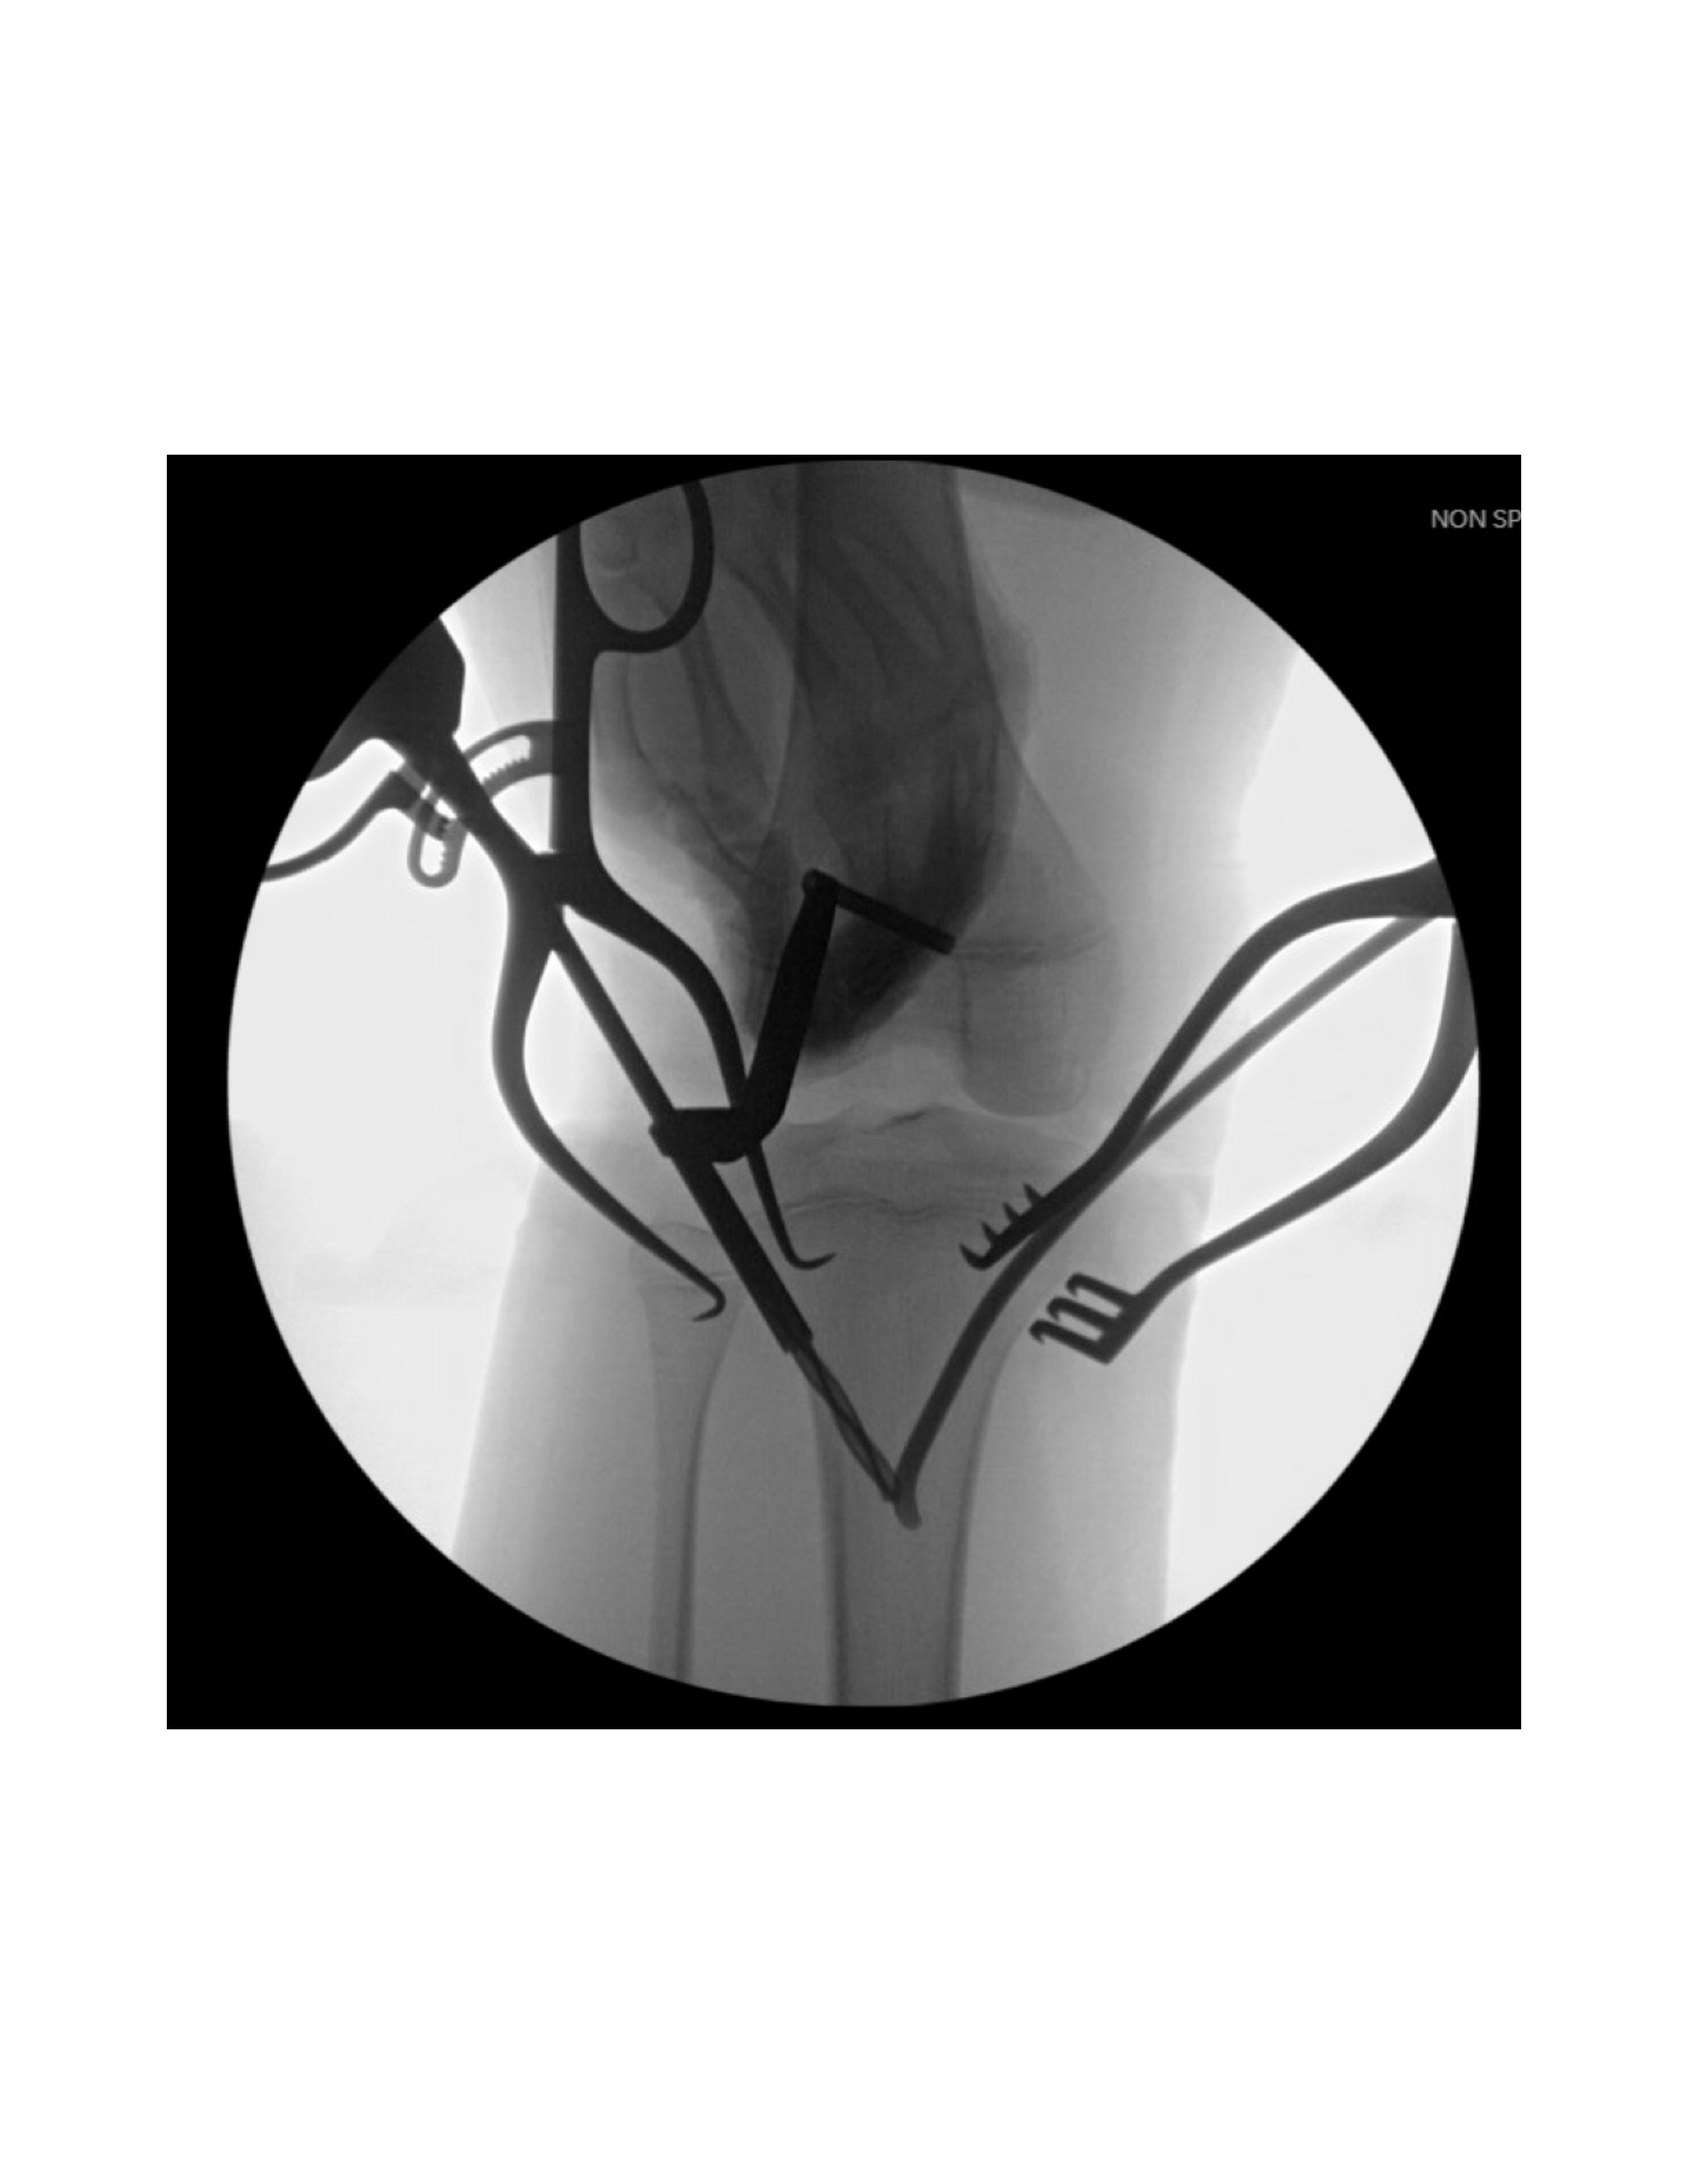

Next, lateral entry point is made with a 2-3 cm longitudinal incision over the anterior compartment musculature between the tibial crest and the fibula head, 10-30 mm distal to the proximal physis. After blunt dissection, fascia splitting anteriorly, and lifting the anterior 6 compartment musculature off the tibia, a drill is utilized under fluoroscopy to enter the cortex anterior to the lateral border of the interosseous membrane attachment site. The modified nail is inserted using an inserter/T-handle with the curved tip perpendicular to the medial cortex (Figure 3). Oscillatory motions facilitate entry into the medullary canal until contact is made with the far cortex. The nail is then advanced by a mallet proximal to the fracture site before addressing the medial nail.

A similar incision is made over the medial tibia, 10-30 mm distal to the proximal physis. After blunt dissection to the bone posterior to the midsection of the medial metaphysis, a drill is utilized under fluoroscopy to create an entry hole between the pes anserine tendons and the medial collateral ligament insertion site. The modified nail is inserted similarly (Figure 4).